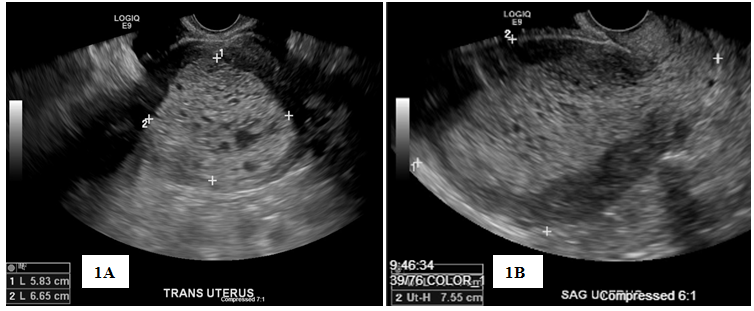

Patient was lost to follow-up until she presented in May 2018 for irregular bleeding and endometrial biopsy showed endometrial hyperplasia with atypia suspicious for adenocarcinoma; endocervical curettage and endocervical polyp showed similar pathology. Pap screen and HPV were negative for intraepithelial lesion or malignancy; CA-125 was 43.4. Pelvic sonogram showed the uterus (11.3 by 7.6 by 8.5) with an endometrial mass (10.5 by 5.8 by 6.6) (Figure 1). In addition, there was a 19-mm cyst in the right ovary (Figure 1). On review of the sonogram, the endometrial mass is heterogenous and extended into the endocervical os (Figure 1). Concurrent chest x-ray was within normal limits with no abnormalities; CT of the chest, abdomen, and pelvis (Figure 2) was negative for chest and liver metastasis and hydronephrosis; positive for 7-mm paraaortic node, 9-mm pelvic node, right ovarian cyst (2.8-cm), and an endometrial mass (6.7 by 6.4-cm). Physical exam showed midline cervix 2.0 cm in diameter, soft but with 4 by 5 mm ass protruding from the cervical os. Uterus is 12 by 10 by 8 cm anterior not tender. Adnexa were not appreciated and no nodularity in the cul de sac. The patient was started on Megace 40mg daily. At this time, hysterectomy, bilateral salpingo-oophorectomy and staging were indicated.

Figure 1 Pelvic Ultrasound, Transverse view (1A) and Sagittal view (1B) showing endometrial mass measuring 10.5×5.8×6.6cm, highly suspicious for endometrial neoplasia.